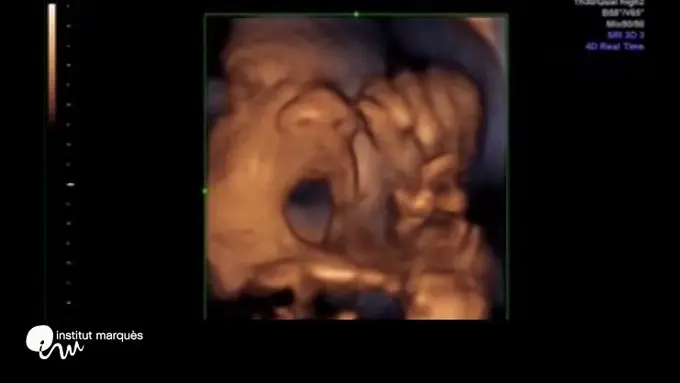

Fimela.com, Jakarta Janin, yang notabene masih terbilang sebagai embrio di dalam kandungan, rupanya bisa memberikan respon ketika diperdengarkan suara musik. Hal tersebut terbukti dari jurnal yang dipublikasikan oleh British Medical Ultrasound Society mengenai janin berusia 16 minggu yang menggerakkan mulut saat diperdengarkan suara musik. Penelitian yang dilakukan oleh tim ilmuwan Spanyol ini direkam menggunakan USG 3 Dimensi/4 Dimensi dengan meletakkan speaker di dalam vagina ibu hamil.

Dari hasil studi tercatat kalau janin dari usia 16 minggu memiliki respon dengan menggerakkan mulut dan lidah. Jika dipersentase, 87 persen janin menggerakkan mulut, dan 46 persen menggerakkan lidah mereka. Para peneliti yang diketahui dari Instituto Marques mengklain bahwa ini adalah pertama kalinya seseorang menimbulkan gerakan tertentu pada janin.

Kesimpulan dari penelitian ini menunjukkan bahwa jalur syaraf berpartisipasi dalam sistem motor pendengaran yang dikembangkan pada usia 16 minggu kehamilan. Para peneliti berharap agar penelitian ini bisa berkontribusi untuk screening pendengaran sebelum melahirkan dan stimulasi saraf pada janin. Sebagai tambahan, para peneliti mengatakan bahwa memperdengarkan musik ke janin bisa mengaktifkan sirkuit otak yang terlibat dalam bahasa dan komunikasi. Mereka juga menyarankan proses belajar dimulai dari dalam rahim.